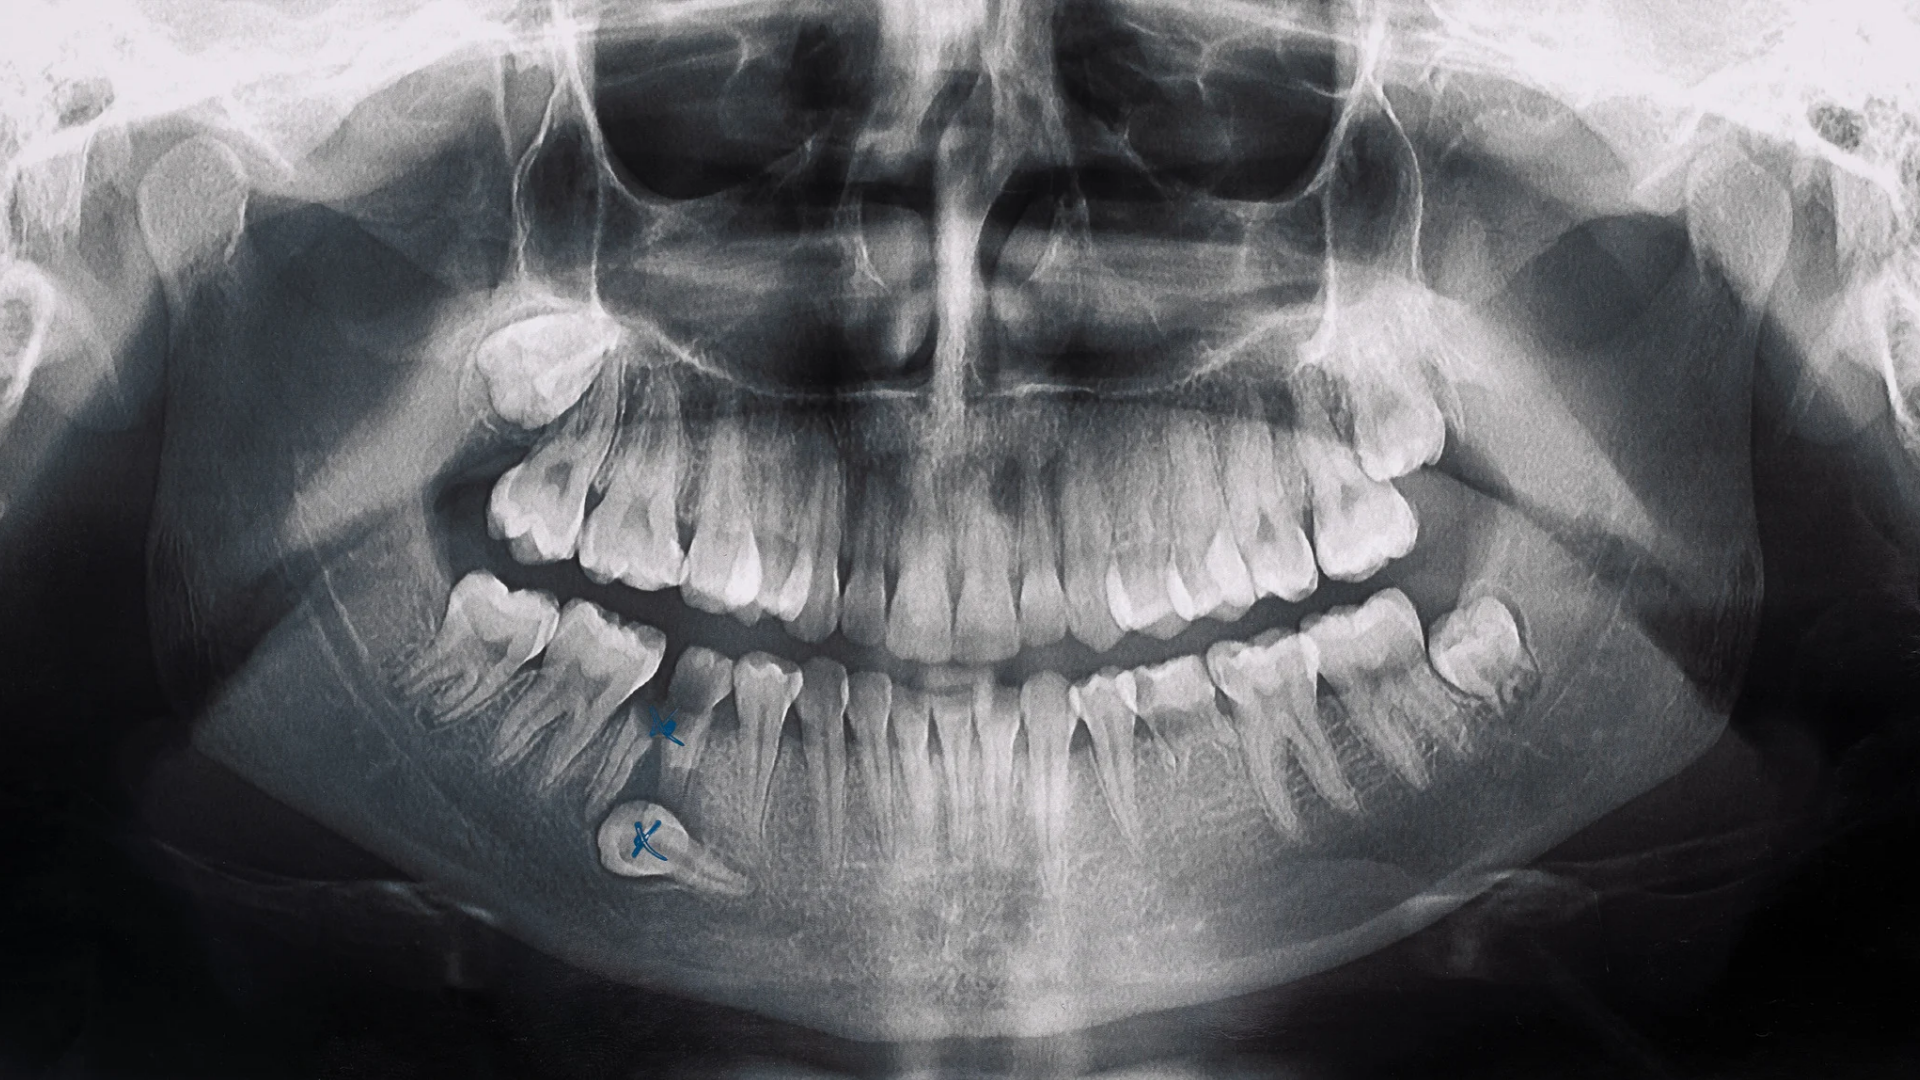

¿Necesitas imágenes tridimensionales precisas? Nuestras tomografías 3D te brindan diagnósticos milimétricos para planificación de tratamientos.

¿Buscas análisis biomecánicos avanzados? Nuestros estudios Orthokinética 2D te ofrecen evaluaciones detalladas para tratamientos personalizados.

¿Necesitas estudios adicionales? Ofrecemos radiografías especializadas, reportes detallados y análisis de ATM para diagnósticos completos.